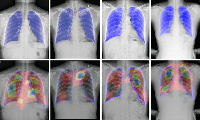

Изучение проблемы низкого качества рентгенограмм на Вашем оборудовании.